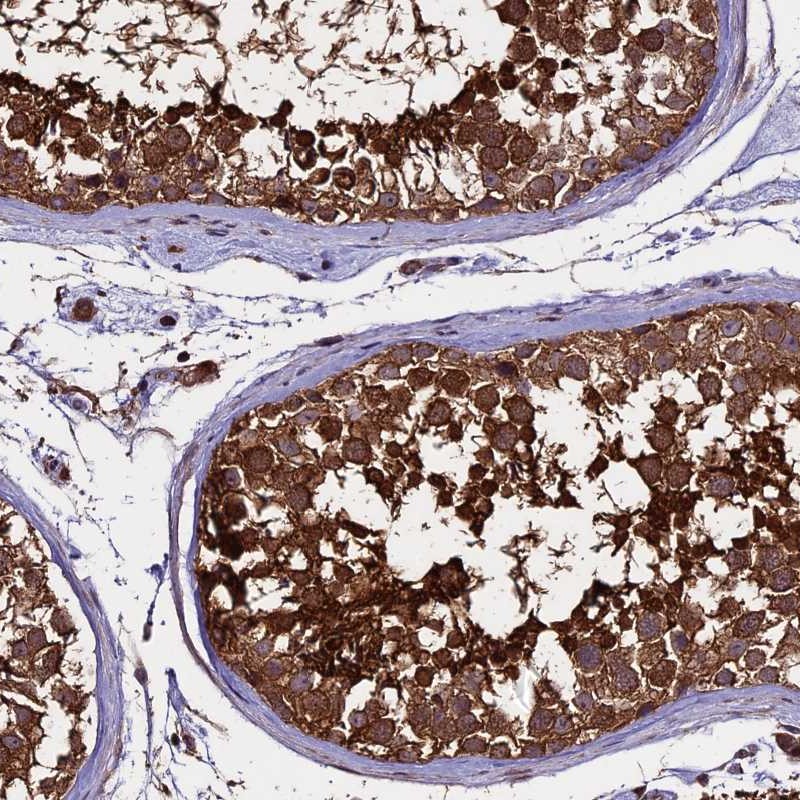

Immunohistochemical staining of human testis shows strong cytoplasmic positivity in cells in seminiferus ducts.